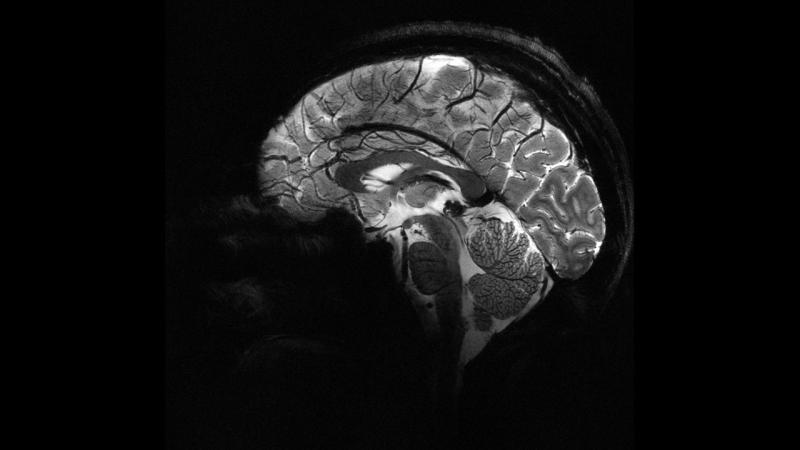

İngiltərədə aparılan bir araşdırmaya görə, insanların beyni COVID-19 dövründə 2020-ci ildən əvvəlki ilə müqayisədə orta hesabla 5,5 ay daha sürətli qocalıb.

7News.Az xarici mətbuata istinadən xəbər verir ki, Nottingem Universitetinin alimləri Böyük Britaniya Biobankında 15 000-dən çox insanın məlumatlarından istifadə edərək sağlam beyin yaşlanmasını tanıyan süni intellekt modeli hazırlayıblar.

Model pandemiyadan əvvəl skan edilənlərin beyin yaşlarını pandemiyadan əvvəl və pandemiya zamanı skan edilənlərlə müqayisə edib.

Araşdırmaya görə, pandemiya zamanı insan beyninin qocalma sürəti orta hesabla 5,5 ay sürətlənib.

Tədqiqatda vurğulanıb ki, beyin yaşının artması mütləq geriləmə yaını azaltmır; koqnitiv tənəzzül yalnız virusa yoluxanlarda aşkar edilib.